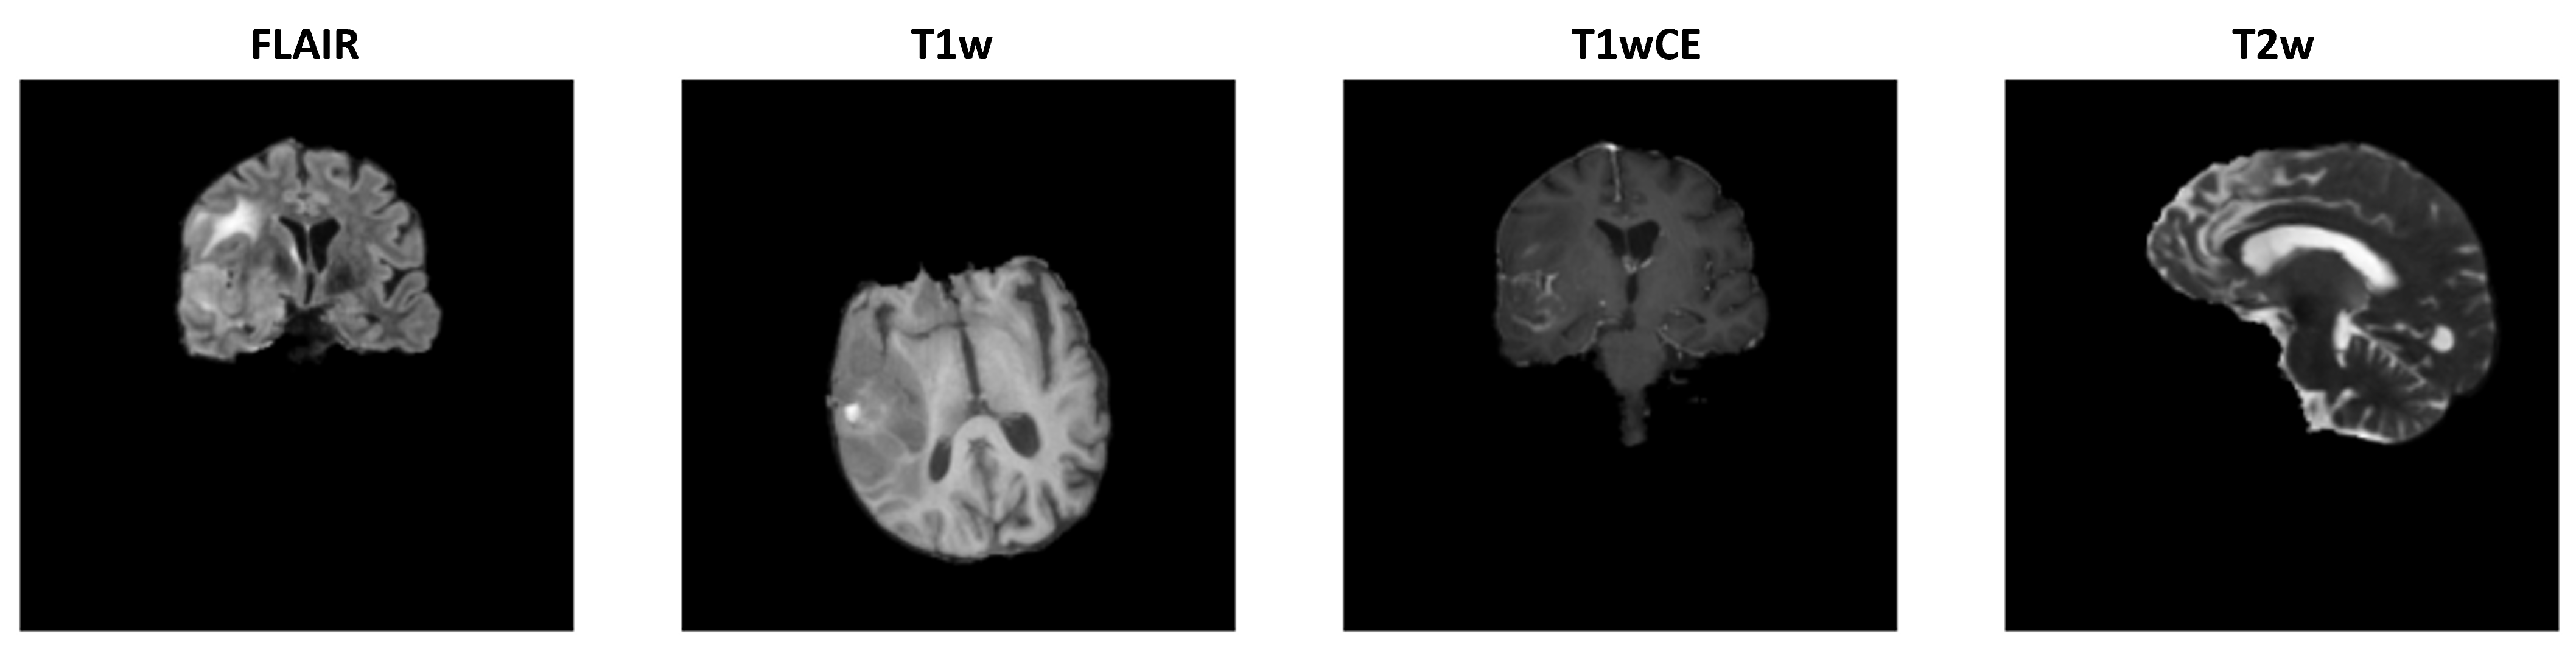

The dataset used in this study is from the Brain Tumor Radiogenomic Classification challenge [Baid et al.(2021)Baid, Ghodasara, Mohan, Bilello, Calabrese, Colak, Farahani, Kalpathy-Cramer, Kitamura, Pati, et al.] that includes multi-parametric MRI (mpMRI) scans for 585 glioblastoma patients having 348,641 scans. It was split to 80% training data and 20% testing data. Patients with IDs [00109, 00123, 00709] were removed from the dataset due to issues present in their images. The patients belong to two classes: methylated MGMT and unmethylated MGMT. The dataset is balanced, containing 307 methylated cases and 278 unmethylated cases. Images are in DICOM format that comes with an associated header including clinical information such as modality, orientation, and MRI machine-specific details. Each patient has images in four different modalities: T1-weighted pre-contrast (T1), T1-weighted post-contrast (T1wCE (Gadolinium)), T2-weighted (T2), and T2 Fluid Attenuated Inversion Recovery (T2-FLAIR). The number of slices for each patient differ. MRI images come in three orientations, including coronal, axial, and sagittal. In all the experiments in this manuscript, we use FLAIR or T1wCE type images as the tumor appears bright and easier to distinguish; tumor is thought to encode the information concerning the MGMT promoter state. \figurereffig:Dataset shows four random slices displaying the four modalities and the existence of different orientations for the same patient. The brain images provided are already pre-processed by being co-registered to the same anatomical template (SRI24), resampled to a uniform isotropic resolution, and skull stripped. The Brain Tumor Radiogenomic Classification challenge dataset includes images from various collections such as the TCIA [Clark et al.(2013)Clark, Vendt, Smith, Freymann, Kirby, Koppel, Moore, Phillips, Maffitt, Pringle, et al.] public collection of TCGA-GBM, ACRIN-FMISO-Brain collection (ACRIN 6684)[Gerstner et al.(2016)Gerstner, Zhang, Fink, Muzi, Hanna, and Greco, Kinahan et al.(2018)Kinahan, Muzi, Bialecki, and Coombs], and other public and private datasets. The following preprocessing steps were performed in this study for all the experiments: 1) Resampling the scans to the axial plane for consistency. 2) For 3D experiments, extracting the same number of slices for each patient. If any further preprocessing steps were performed for an experiment, they would be mentioned in the relevant sections.